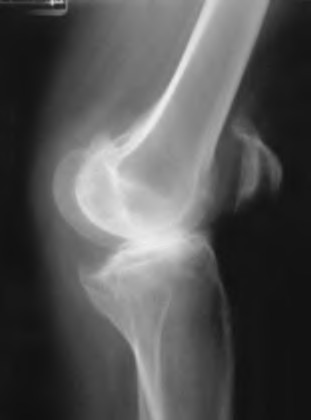

The radiograph seen in Figure A reveals varus alignment of the knee, with medial tibial deficiency; from this X-ray the patient appears to have unicompartmental arthritis. Treatment options for unicompartmental arthritis include high tibial osteotomy, interpositional arthroplasty, unicondylar knee replacement and total knee replacement. Interpositional arthroplasty became popular in the 1950’s when early outcomes analysis seemed to indicate good results; long term follow up in one study found 0/12 excellent results, with all patients requiring conversion to TKA. This procedure is no longer recommended due to the poor long term outcomes.

While an osteotomy is still used for young and active patients, unicompartmental or total knee arthroplasty have largely replaced this treatment in older patients. Advantages of UKA and TKA include more predictable relief of pain, quicker recovery, and better long-term results. Criteria for UKA include limited unicompartmental disease, no more than a fixed 10 degrees of varus or 5 degrees of valgus deformity from neutral and an intact anterior cruciate ligament with no signs of medial lateral subluxation of the femur on the tibia; this patient is therefore not a good candidate for this procedure.

Total knee arthroplasty can be used to provide predictable pain relief in a patient with unicompartmental and tricompartmental degenerative disease and varus malformation of the knee and for this patient is the best option.